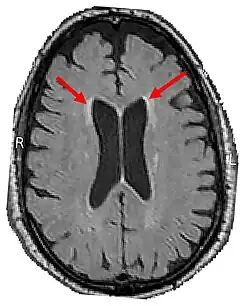

LENAS is seen with damage to the white matter and axons within the brain. The external human LENAS brain shows findings in several major structures. There is mild atrophy of the frontoparietal regions of the brain and a mild reduction of the thalamus and rostral (front) part of the caudate nucleus (which is located in an area of the brain called the basal ganglia).[5] Abnormalities in the frontal, frontoparietal, and temporal lobes are most severe and predominant with LENAS and asymmetry of the cerebral hemispheres has sometimes been found.[5] LENAS also may show moderately enlarged lateral ventricles and atrophy in corticospinal tracts as well as in the pons.[5]